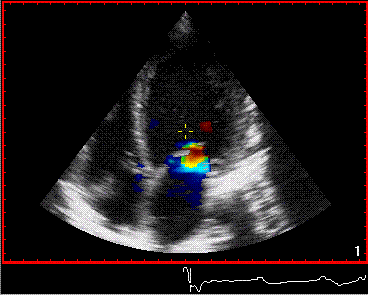

رنگین ڈوپلر الٹراساؤنڈ خون کے بہاؤ کو ظاہر کرنے کے لیے استعمال کیا جاتا ہے۔ یہ خون کے بہاؤ کی سمت اور رفتار کو ظاہر کرنے کے لیے مختلف رنگوں اور چمک کا استعمال کرتا ہے، جس سے ہمیں خون کی شریانوں اور دل کا مشاہدہ کرنے میں مدد ملتی ہے۔

بعض اوقات ڈاکٹروں کو خون کے بہاؤ کی لہر کا درست مشاہدہ کرنے کی ضرورت ہوتی ہے، اور اس کی رفتار کی پیمائش کرتے وقت، وہ دوسرے الٹراساؤنڈ پر جائیں گے: ڈوپلر الٹراساؤنڈ۔ حاملہ مائیں تین جہتی اور سے سب سے زیادہ واقف ہوسکتی ہیں۔چار جہتی الٹراساؤنڈ